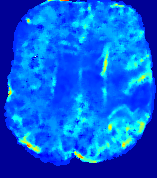

LesionRefer to captionRefer to captionRefer to captionRefer to captionRefer to captionRefer to caption𝐕rgbsubscript𝐕𝑟𝑔𝑏{\bf{V}}_{rgb}Refer to captionRefer to captionRefer to captionRefer to captionRefer to captionRefer to caption𝐕2subscriptnorm𝐕2{\|\bf{V}}\|_{2}Refer to captionRefer to captionRefer to captionRefer to captionRefer to captionRefer to captionRefer to caption3.53.53.52.82.82.82.12.12.11.41.41.40.70.70.70.00.00.0(mm/s)𝑚𝑚𝑠(mm/s)D𝐷DRefer to captionRefer to captionRefer to captionRefer to captionRefer to captionRefer to captionRefer to caption0.0200.0200.0200.0160.0160.0160.0120.0120.0120.0080.0080.0080.0040.0040.0040.0000.0000.000(mm2/s)𝑚superscript𝑚2𝑠(mm^{2}/s)Slice #1Slice #2Slice #3Slice #4Slice #5Slice #6

Figure 3: PIANO feature maps for one stroke patient, where the lesion is located in the left hemisphere. Top row: segmented stroke lesion region (white) on different slices, obtained from ISLES 2017. The corresponding slices for the PIANO feature maps are shown in the following rows.

For a better insight into an estimated velocity field 𝐕𝐕{\bf{V}} and diffusion field 𝐃𝐃{\bf{D}}, we compute the following maps: (1) 𝐕rgbsubscript𝐕𝑟𝑔𝑏{\bf{V}}_{rgb}: Color-coded orientation map of 𝐕=(Vx,Vy,Vz)T𝐕superscriptsuperscript𝑉𝑥superscript𝑉𝑦superscript𝑉𝑧𝑇{\bf{V}}=(V^{x},V^{y},V^{z})^{T}, obtained by normalizing 𝐕𝐕{\bf{V}} to unit length and mapping its 3 components to red, green, blue respectively; (2) 𝐕2subscriptnorm𝐕2\|{\bf{V}}\|_{2}: 222 norm of 𝐕𝐕{\bf{V}}; (3) D𝐷D: scalar field in Eq. 5.

Fig. 3 and Fig. 4 show the PIANO feature maps estimated from two ISLES 2017 patients: all are highly consistent with the lesion in both cases. Details of the blood flow trajectories are revealed in 𝐕rgbsubscript𝐕𝑟𝑔𝑏{\bf{V}}_{rgb} by the ridged patterns and the sharp changes of colors in the unaffected (right) hemisphere, while the flat patterns appearing within the lesion provide little directional information about the velocity and indicate low velocity magnitudes. Velocity magnitudes are more directly visualized via 𝐕2subscriptnorm𝐕2\|{\bf{V}}\|_{2}, from which one can easily locate the lesion where 𝐕2subscriptnorm𝐕2\|{\bf{V}}\|_{2} is low. D𝐷D also indicates lower diffusion values in the lesion, though with less contrast potentially due to the fact that it captures the accumulated effect of CA diffusion at the voxel-level.